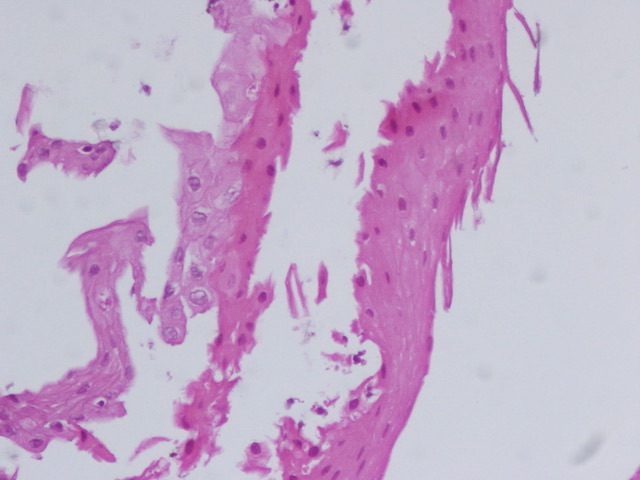

#GIPath #Diagnosethis #Pathresidents 1/2 Look what crossed my my microscope ? The key is in the bitonal hue of this esophagus with sharply demarcated layers ,strong pink superficial ,intraepithelial cleft ,partially detached ,other fragments with just strips of superficial

6

24

69